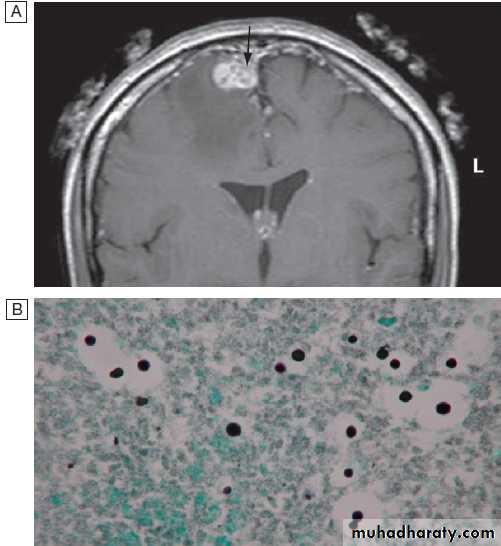

HSV is the leading cause of sporadic viral encephalitis , this serious complication may occur following either primary or secondary disease, usually with HSV-1. A haemorrhagic necrotising temporal lobe cerebritis produces temporal lobe epilepsy and altered consciousness/coma. Without treatment, mortality is 80%. HSV is also implicated in the pathogenesis of Bell’s palsy with a lower motor neuron VII nerve palsy, although antivirals have not been demonstrated to improve outcome.